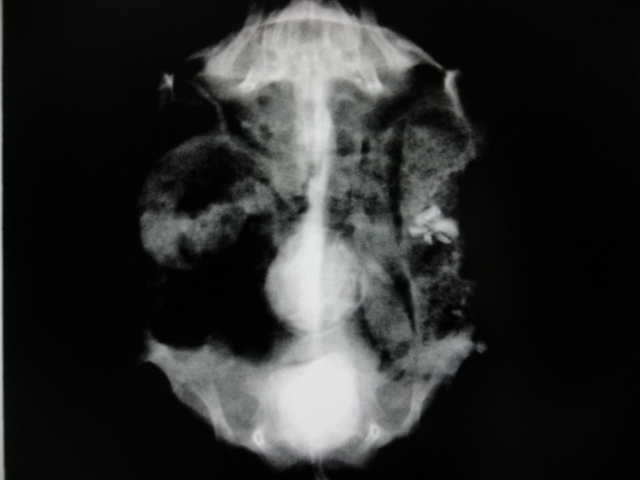

下のレントゲン写真の子は、膀胱内と総排泄腔に結石を認めました。

膀胱内に結石があるうちにはほとんど症状を示すことはありませんが、

膀胱から出て骨盤腔内や総排泄腔などで詰まってしまうと、

排尿困難や排便困難などを引き起こし、激しいいきみなどの症状を表します。

そうなると全身麻酔下での摘出を行う必要があります。